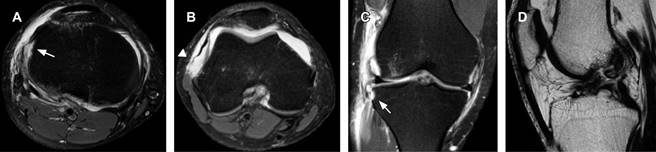

Figura 2: A y B) Axial T2W FS. A) Avulsión ósea a nivel de la inserción tibial del ligamento anterolateral (flecha). B) El retináculo lateral muestra pérdida de su tensión y elongación en relación a ruptura completa (punta de flecha) en su inserción femoral. C) Imagen coronal T2W FS en la cual se delimita el ligamento anterolateral en su inserción femoral, meniscal, y a nivel de la inserción tibial (flecha) con fragmento óseo avulsionado (fractura de Segond). D) Sagital T2SE. Ruptura completa del ligamento cruzado anterior.

Masculino de 32 años, el cual refiere dolor agudo y edema localizado en la rodilla derecha secundario a rotación interna e hiperextensión al practicar fútbol soccer. Acude al servicio de urgencias donde se solicitan proyecciones radiográficas anteroposterior y lateral de rodilla derecha, identificando una imagen radiopaca vertical, localizada adyacente al borde tibial lateral, en relación a fractura por avulsión (Figura 1). Se complementa estudio con resonancia magnética en la cual se demuestra una ruptura completa del ligamento cruzado anterior (LCA) y del retináculo lateral, confirmando la fractura por avulsión de la meseta tibial a nivel de la inserción del ligamento anterolateral (LAL) (Figura 2).